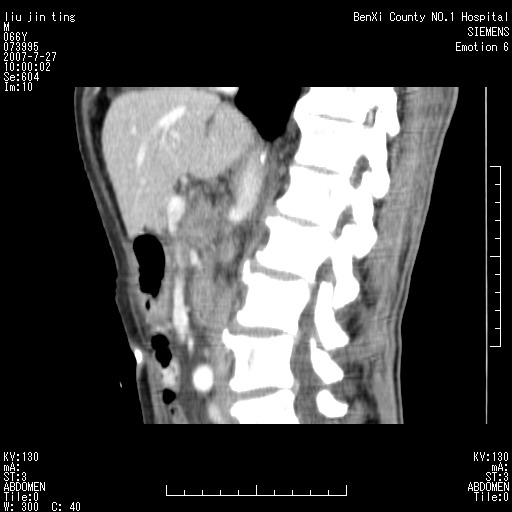

腹痛,背痛,无恶心呕吐,不黄,彩超示胰腺钩癌,ct扫描病灶平扫30-40hu,增强后动脉期40--60hu,静脉期50-68hu,真的是钩突上的么?您要试一试么?

静脉期

沿着肠系膜上动脉呈匍匐性生长的软组织肿块,形态不规则,包绕肠系膜上动脉,呈明显强化,考虑来源于肠系膜的恶性肿瘤

沿着肠系膜上动脉呈匍匐性生长的软组织肿块,形态不规则,包绕肠系膜上动脉,呈轻-中度强化,考虑来源于肠系膜的恶性肿瘤。

钩突是正常的,只见腹膜后淋巴结的肿大,考虑淋巴瘤或转移可能。